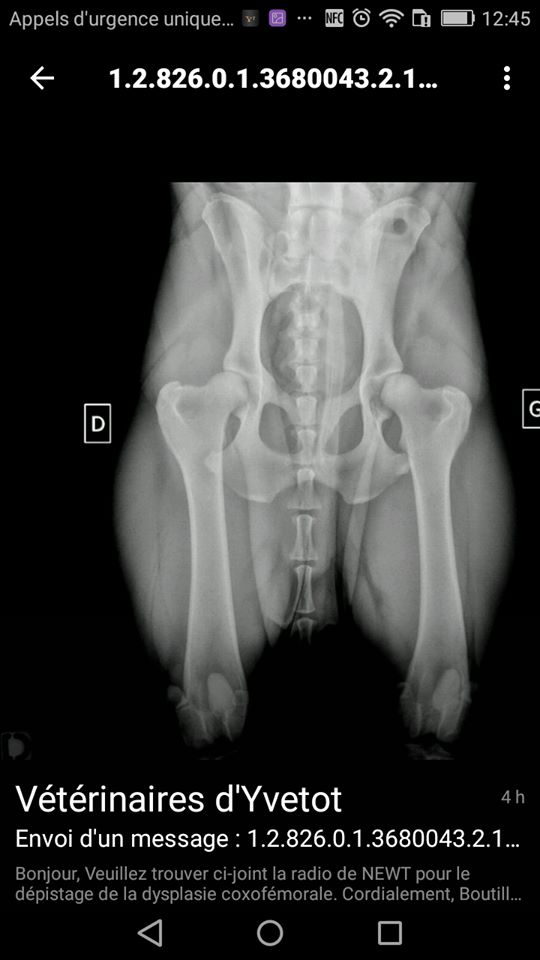

dysplasie A/B